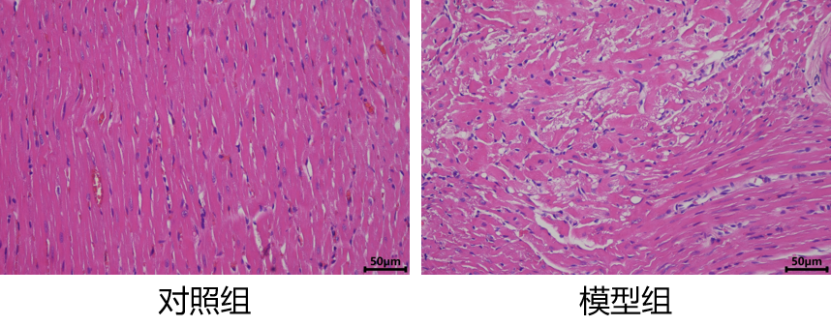

2.心肌组织HE染色

2. HE染色进行心肌组织病理观察,正常组心肌排列整齐;模型组心肌组织中大量弥漫性出血,出血灶周围心肌细胞核形态发生变化,大量炎性细胞浸润。